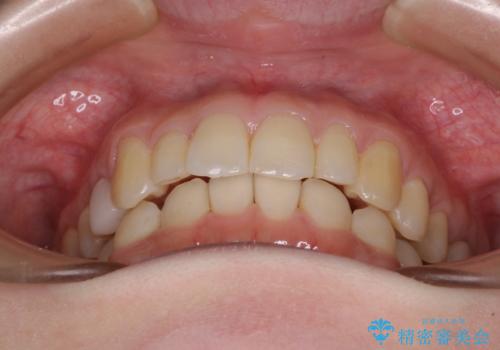

- 上顎前歯の突出感を気にして来院された患者様です。

下顎前歯2本が先天欠損しており、上顎歯列に対して、下顎歯列がアンバランスに小さい状況でした。

左右上顎側切歯2本が矮小歯であるため、上顎の抜歯ではなく、IPR(歯と歯の間を削る)と歯列全体の後方移動によってバランスを整えることとしました。

目立ちにくい装置を希望されたため、インビザラインにて治療を行うこととしました。

歯列のバランスが悪く、インビザライン矯正特有の奥歯の噛みにくさがなかなか改善されず、治療期間が長期化してしまいました。